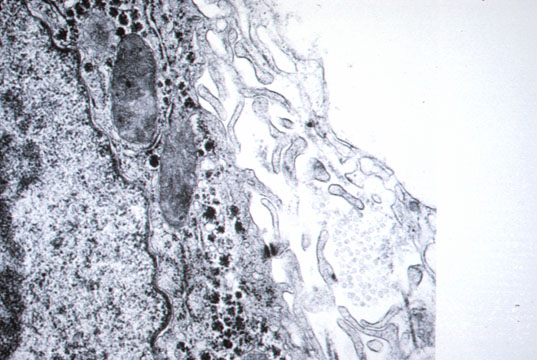

Space of Disse

Fig 18 - A space that can be visualized only by electron microscopy between endothelial sinusoidal wall and hepatocyte.Numerous villi of hepatocytes float in this space obviously to increase their absorptive capacity. Only plasma filtrated by the endothelium flows in it. No blood cells. It contains different types of collagen,mainly type I and IV with proteoglycans an fibronectin.

Lipocytes

Fig 19 - ITO CELLS (Lipocytes) They are perisinusoidal cells more frequent in zone 3. They have fat vacuoles and indented nuclei.Positive for desmin under immuno stain, especially on frozen sections. They store vitamin A and produce perisinusoidal reticulum. They become hyperplastic in hypervitaminosis A. Pitt cells Are hepatic Natural Killer cell present in rat liver sinusoids. They have a higher level of activation and different morphology than NK cells of the blood.They are large ,granular lymphocytes in contact with endothelial and Kupffer cells and can be identified with electron microscopy. Their role is probably a defence against viruses and tumors.